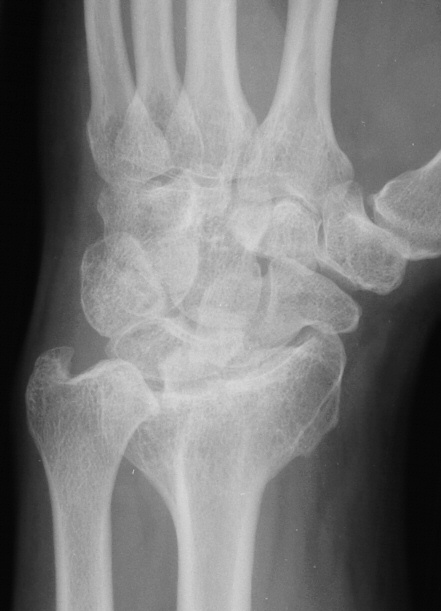

Clinical Example: Radioscapholunate Fusion and Triquetrum excision for Radiocarpal Arthritis

Radioscapholunate fusion is a treatment option for radiocarpal arthritis following distal radius fracture or associated with rheumatoid arthritis. Range of motion is usually less than half of normal following this procedure. Technical modifications to improve range of motion include distal scaphoid excision, or as in this case, triquetrum excision and excision of distal ulnar articular surface to manage ulnolunate abutment. There are a variety of fixation techniques. In this case, crossed Herbert screws were used: dorsal carpal bone to palmar radius and dorsal radius to palmar carpal bone.

Preoperative Xrays: